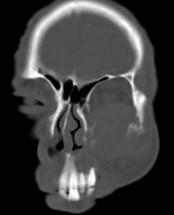

问题 男,65岁,左眼球突出近1年,鼻涕带血,面颊部隆起,同时面颊部有麻木感,CT检查如图,最可能诊断为()

选项 A.上颌窦息肉 B.上颌窦血管瘤 C.上颌窦囊肿 D.上颌窦癌 E.骨肉瘤

答案 D